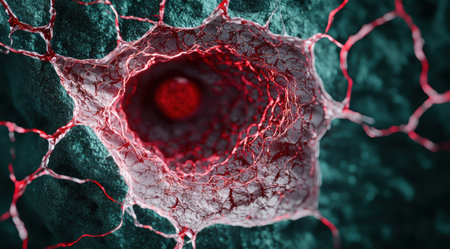

Microscopic view of a blood vessel